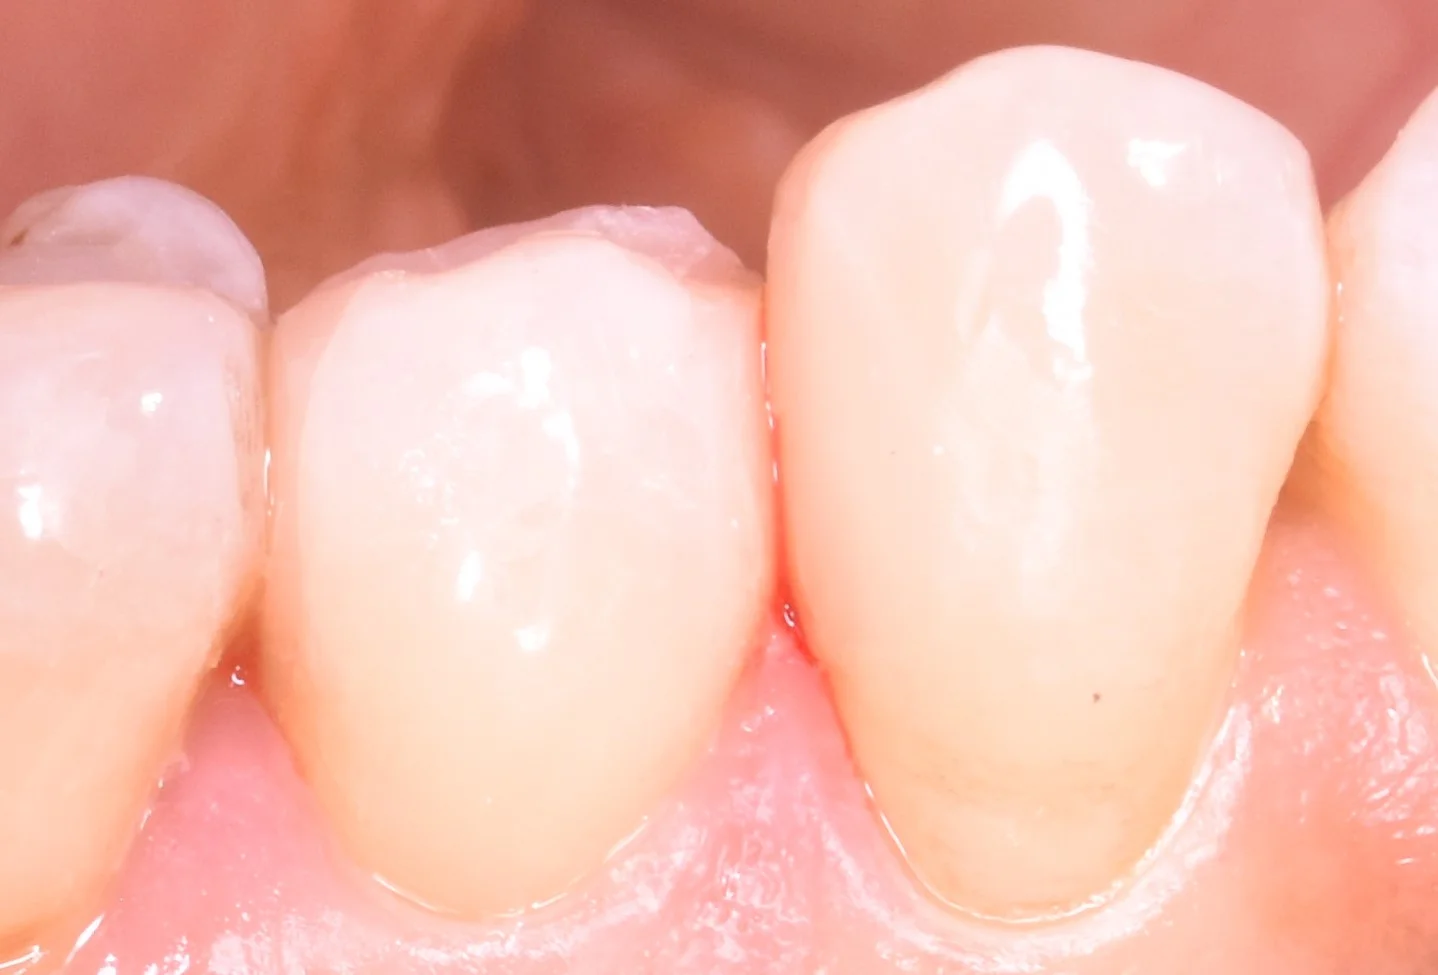

想定よりも大きく歯が無くなってしまっていたので、今回、側面の写真も撮りました。

それがこちらになります。

奥歯の歯並びが悪くなってしまっている所の治療|坂寄歯科医院(取手市藤代) - 画像4

こう見るとどれほど大きな虫歯だったのか想像できるかと思います。

そして虫歯を詰め終わったのがこちらです。

奥歯の歯並びが悪くなってしまっている所の治療|坂寄歯科医院(取手市藤代) - 画像5

術前の状態では手前の歯に刺さるような状況になっていたのですが、その形態だとまた虫歯になりやすくなっちゃうと思いましたので、清掃性を優先して自然な形で当たるように詰めました。